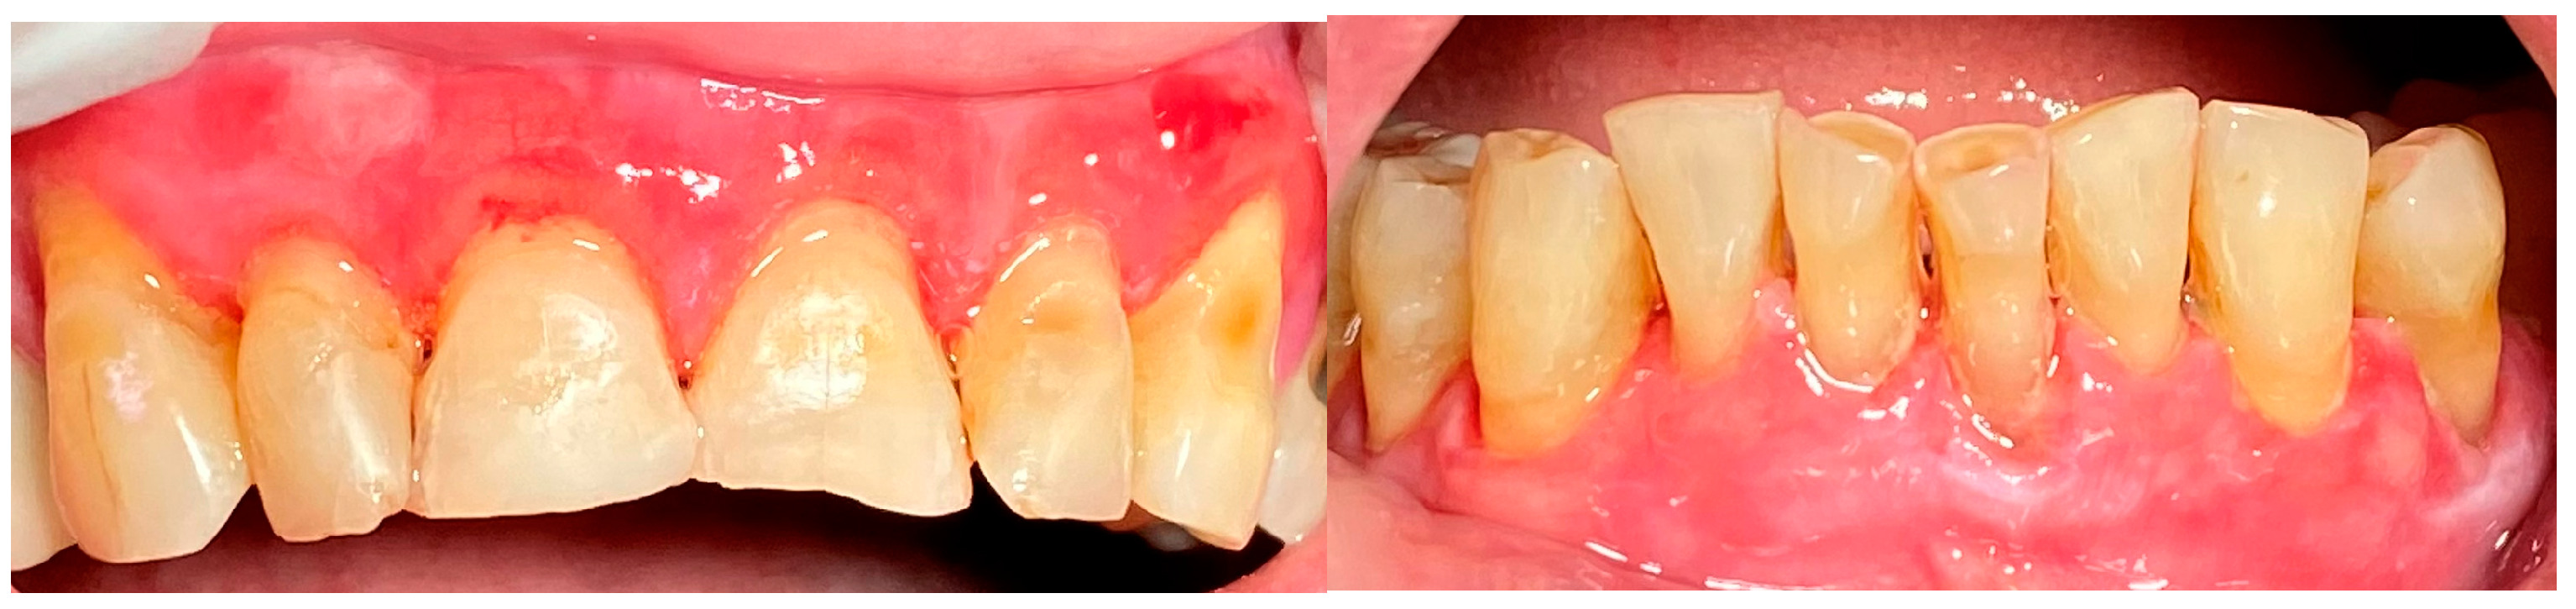

2.1. Clinical Case 1—Mucous Membrane Pemphigoid (MMP)

2.2. Clinical Case 2—Pemphigus Vulgaris (PV)

2.3. Clinical Case 3—Oral Lichen Planus (OLP)